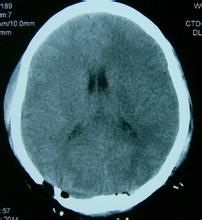

主要是急性腦病如腦卒中、腦出血、腦梗死,各型腦外傷等病所引起。

診斷

根據病史和臨床特點,心電圖特徵即可診斷。